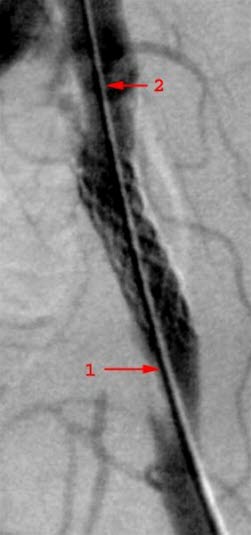

Diagnosen kan om nødvendig bekreftes ved ultralyd. Eventuelt gjøres også røntgen, CT eller MR som forberedelser til operasjon.

Kirurgi med blokking av trange partier i blodåren, eller utskifting av blodårer (by-pass), kan i noen tilfeller være nødvendig for å lindre plager. Slik behandling er imidlertid ikke livsforlengende. Operasjon gjøres kun der alle behandlingsalternativer er forsøkt uten tilstrekkelig effekt. Operasjon er også nødvendig dersom det er akutt fare for koldbrann.